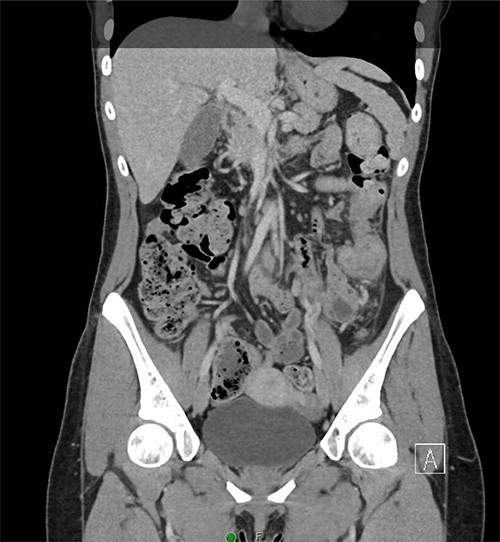

A 31-year-old woman initially presented to the ED with 2 days of left flank pain and a 1-year history of abdominal pain and bloating. The patient reported having had a fever (100.5 Tmax) and recurrent non-bloody loose stools. Vitals upon presentation to the ED were reassuring and the patient was afebrile. Initial physical exam was normal with the exception of costovertebral angle tenderness. Labs were significant for elevated c-reactive protein and leukocytosis. CT abdomen revealed segmental wall thickening of the descending colon with adjacent inflammation and associated with diverticular disease favoring acute diverticulitis (Figs 1 and 2). There was no evidence of nephrolithiasis. The patient was discharged on a 7-day course of Augmentin and was scheduled for colonoscopy.

After discharge, the patient continued to experience intermittent abdominal pain, melena and diarrhea. These symptoms prompted three more emergency room visits over a 1-month period. Repeat abdominal imaging (CT scan) revealed previously noted colonic inflammation. In addition, colonic intussusception was noted this time. The patient underwent a colonoscopy 2 weeks later revealing a fungating partially obstructing descending colon mass acting as the lead point for intussusception (Fig. 3). The mass was deemed too large for endoscopic removal and multiple biopsies were obtained. These biopsies revealed necrotic granulation tissue without any evidence of malignancy. Patient subsequently underwent an uneventful laparoscopic left hemicolectomy and was discharged home on postoperative Day 3. Final pathology revealed moderately differentiated adenocarcinoma, invading into pericolonic adipose tissue and metastases in 3 of 48 lymph nodes. Immunohistochemistry analysis revealed absence of MLH1, PMS2 and MSH and presence of PSH2, concerning for Lynch Syndrome. Further testing of MLH1 promoter was negative for hypermethylation. The patient was referred to medical oncology for adjuvant chemotherapy. She remains disease free and is on active surveillance for colorectal cancer in setting of Lynch Syndrome.

Axial CT demonstrating segmental wall thickening of the descending colon with adjacent inflammation favoring acute diverticulitis or segmental colitis.